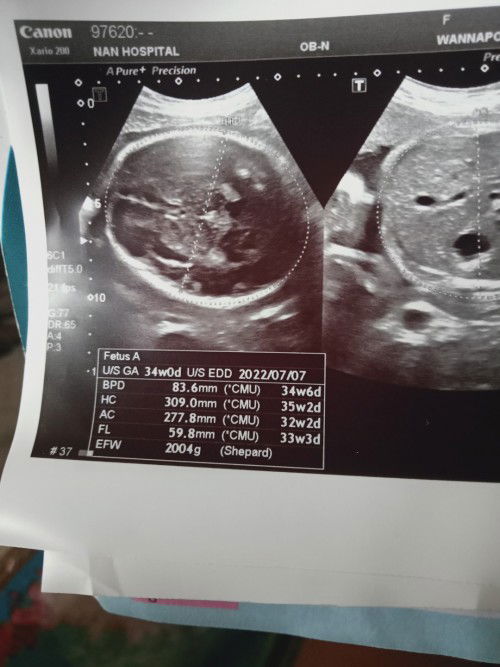

น้ำเราก่อนท้อง 59กิโล ตอนนี้ 8เดือนใกล้9เดือนแล้ว เรา นน.จะ80กิโลแล้ว แต่ในแผ่นอัลตร้าซาวด์น้อง นน.แค่ 2004 กรัม หมอบอกว่าเรา นน.เกิน 5กิโล เรากังวลว่า นน.ที่ขึ้นมาจะลงที่เรามากกว่าลูก มีใครเป็นเหมือนเราบ้างไหมคะ#ขอบคุณล่วงหน้านะคะ

พญาบาลตรวจคลำท้องแล้วเขียนในสมุดให้เรา 32 วีค แต่เราตรวจอัลตราซาวด์บอก 34 วีค เราควรเชื่อแบบไหนคะแม่ๆ #ขอคำแนะนำหน่อยค่ะ #ขอบคุณล่วงหน้านะคะ